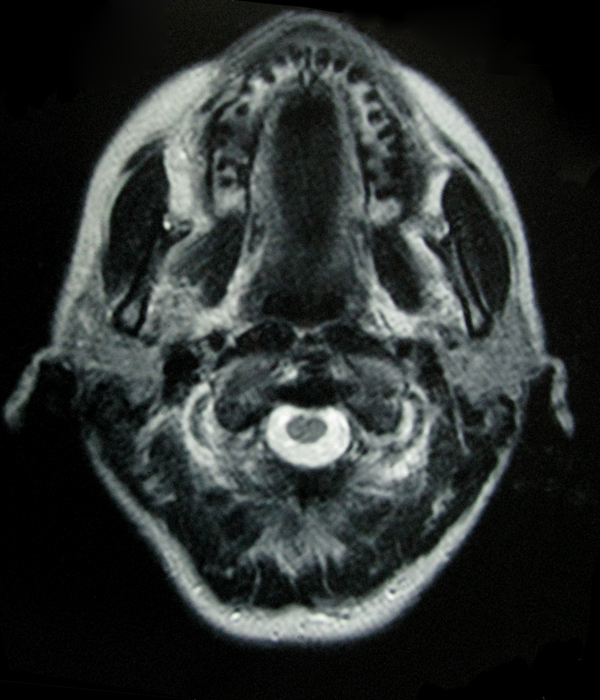

- My Brain in 2009